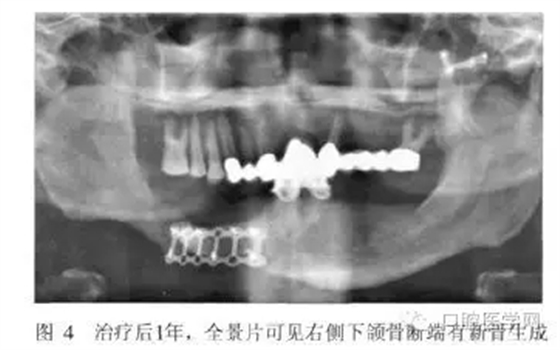

術(shù)后2周和半年進行兩次重襯。治療后半月、3月、6月、1年后復(fù)診,患者的頜面部外貌明顯改善,咀嚼功能提高,義齒使用效果良好(圖3)。全景片示骨斷端有新骨生成(圖4)。

從患者修復(fù)后1年的效果來看,義齒臨床效果良好,X線片示斷端骨密度升高。筆者認為對于類似長期骨愈合不良的斷端,通過適宜的功能刺激及義齒功能狀態(tài)下維持骨斷端的穩(wěn)定,可能有利于促進骨的生長和愈合。